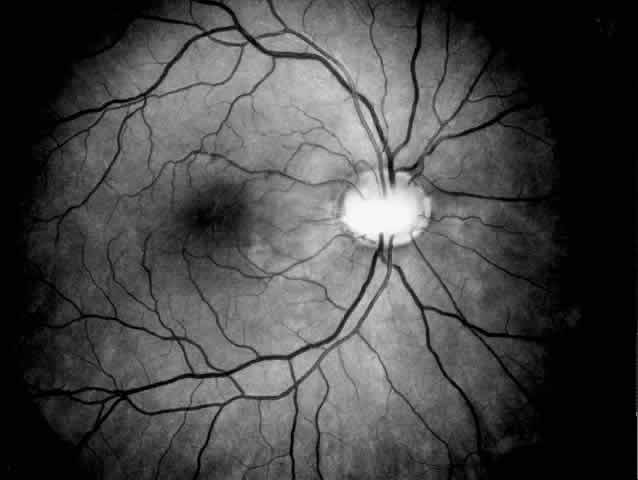

Fig. 2. Papillorenal syndrome with the Handmann optic disc anomaly and macular changes as a result of chronic macular detachment in a renal transplant patient. An optic pit and severe hypertensive changes were observed in his brother, who also received a renal transplant (see Fig. 1). Poor renal function had been recorded in six other family members in three generations.

PAPILLORENAL SYNDROME. The papillorenal syndrome has been defined by Bron18 as a dominantly inherited disorder with a bilateral dysplasia of the optic discs associated with a severe form of glomerulonephritis that may lead to renal failure. The disc anomaly ranges from morning glory anomaly or the Handmann anomaly to coloboma or optic pit (Fig. 2). Optic nerve function may be impaired, and in addition there is a risk of visual loss as a result of serous macular detachment. The pathogenesis of the renal changes and the genetic mechanism linking the renal and ocular abnormalities are unknown.